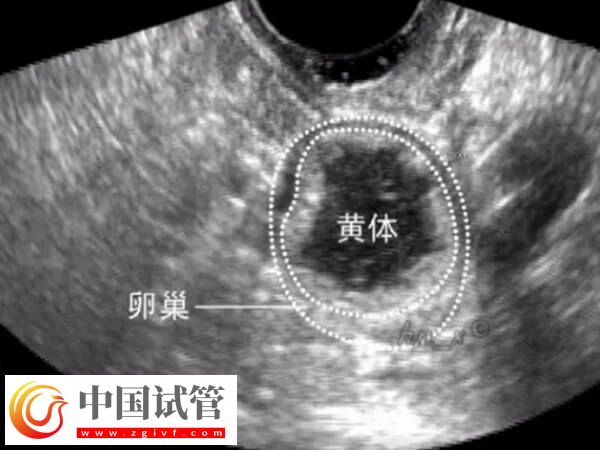

什么是黄体残留

排卵后形成的黄体是一个含有满足受精卵的营养素的蛋白质团。这个结构会释放出大量的孕酮和雌二醇,为身体准备迎接怀孕提供支持。如果在排卵期间使用了药物进行控制,以刺激卵巢产生更多的卵子,黄体就可能在患者体内止于时间较长,也就是产生所谓的“黄体残留”。